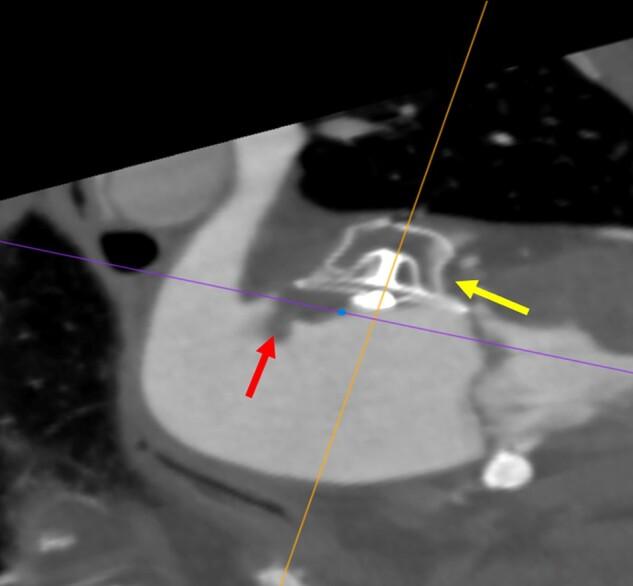

实用的左心耳封堵术非植入医师指南:国际共识文件。

Practical guide on left atrial appendage closure for the non-implanting physician: an international consensus paper.

A significant proportion of patients who suffer from atrial fibrillation (AF) and are in need of thromboembolic protection are not treated with oral anticoagulation or discontinue this treatment shortly after its initiation. This undertreatment has not improved sufficiently despite the availability of direct oral anticoagulants which are associated with less major bleeding than vitamin K antagonists. Multiple reasons account for this, including bleeding events or ischaemic strokes whilst on anticoagulation, a serious risk of bleeding events, poor treatment compliance despite best educational attempts, or aversion to drug therapy. An alternative interventional therapy, which is not associated with long-term bleeding and is as effective as vitamin K anticoagulation, was introduced over 20 years ago. Because of significant improvements in procedural safety over the years, left atrial appendage closure, predominantly achieved using a catheter-based, device implantation approach, is increasingly favoured for the prevention of thromboembolic events in patients who cannot achieve effective anticoagulation. This management strategy is well known to the interventional cardiologist/electrophysiologist but is not more widely appreciated within cardiology or internal medicine. This article introduces the devices and briefly explains the implantation technique. The indications and device follow-up are more comprehensively described. Almost all physicians who care for adult patients will have many with AF. This practical guide, written within guideline/guidance boundaries, is aimed at those non-implanting physicians who may need to refer patients for consideration of this new therapy, which is becoming increasingly popular.

相当一部分患有心房颤动 (AF) 且需要血栓栓塞保护的患者未接受口服抗凝治疗或在开始治疗后不久就停止了治疗。尽管有直接口服抗凝剂可用,其大出血风险低于维生素 K 拮抗剂,但这种治疗不足的情况并未得到充分改善。导致这种情况的原因有很多,包括抗凝期间发生出血事件或缺血性中风、严重出血事件风险、尽管进行了最佳的教育尝试但治疗依从性仍差、或对药物治疗的反感。一种替代的介入治疗方法,它与长期出血无关,与维生素 K 抗凝一样有效,20 多年前就已经引入。由于多年来程序安全性的显著提高,主要通过导管植入设备的方法进行的左心耳封堵术,越来越多地用于预防不能有效抗凝的患者发生血栓栓塞事件。这种管理策略为介入心脏病学家/电生理学家所熟知,但在心脏病学或内科中并未得到更广泛的认可。本文介绍了相关设备并简要解释了植入技术。适应证和设备随访得到了更全面的描述。几乎所有照顾成年患者的医生都会有很多患有 AF 的患者。本实用指南在指南/指导方针的范围内编写,旨在为那些可能需要转介患者考虑这种新疗法的非植入医生提供帮助,这种疗法越来越受欢迎。